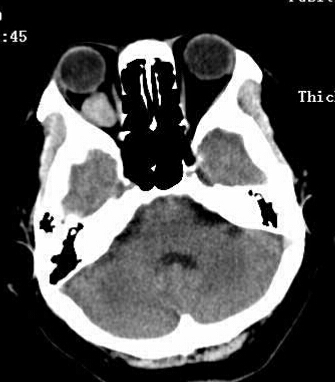

女,54岁,头痛头晕月余,无眼部症状及视力异常。 影像表现:右侧眼球后方占位病变,考虑海绵状血管瘤可能性大,鉴别:视神经鞘瘤、脑膜瘤及炎性假瘤。 病例点评:眼眶内血管瘤是较常见的良性肿瘤,其中以海绵状血管瘤最常见。可发生于任何年龄,主要表现为眼球突出及偏位,在低头或哭泣时可有突眼加重。可经眶缘触及具有压缩性的肿块。视力损害多较缓慢。肿块大多位于肌锥内,其次为肌锥外,平扫呈边界清楚的圆形、卵圆形或分叶状肿块,增强扫描呈缓慢进行性显著强化为其特征性表现。